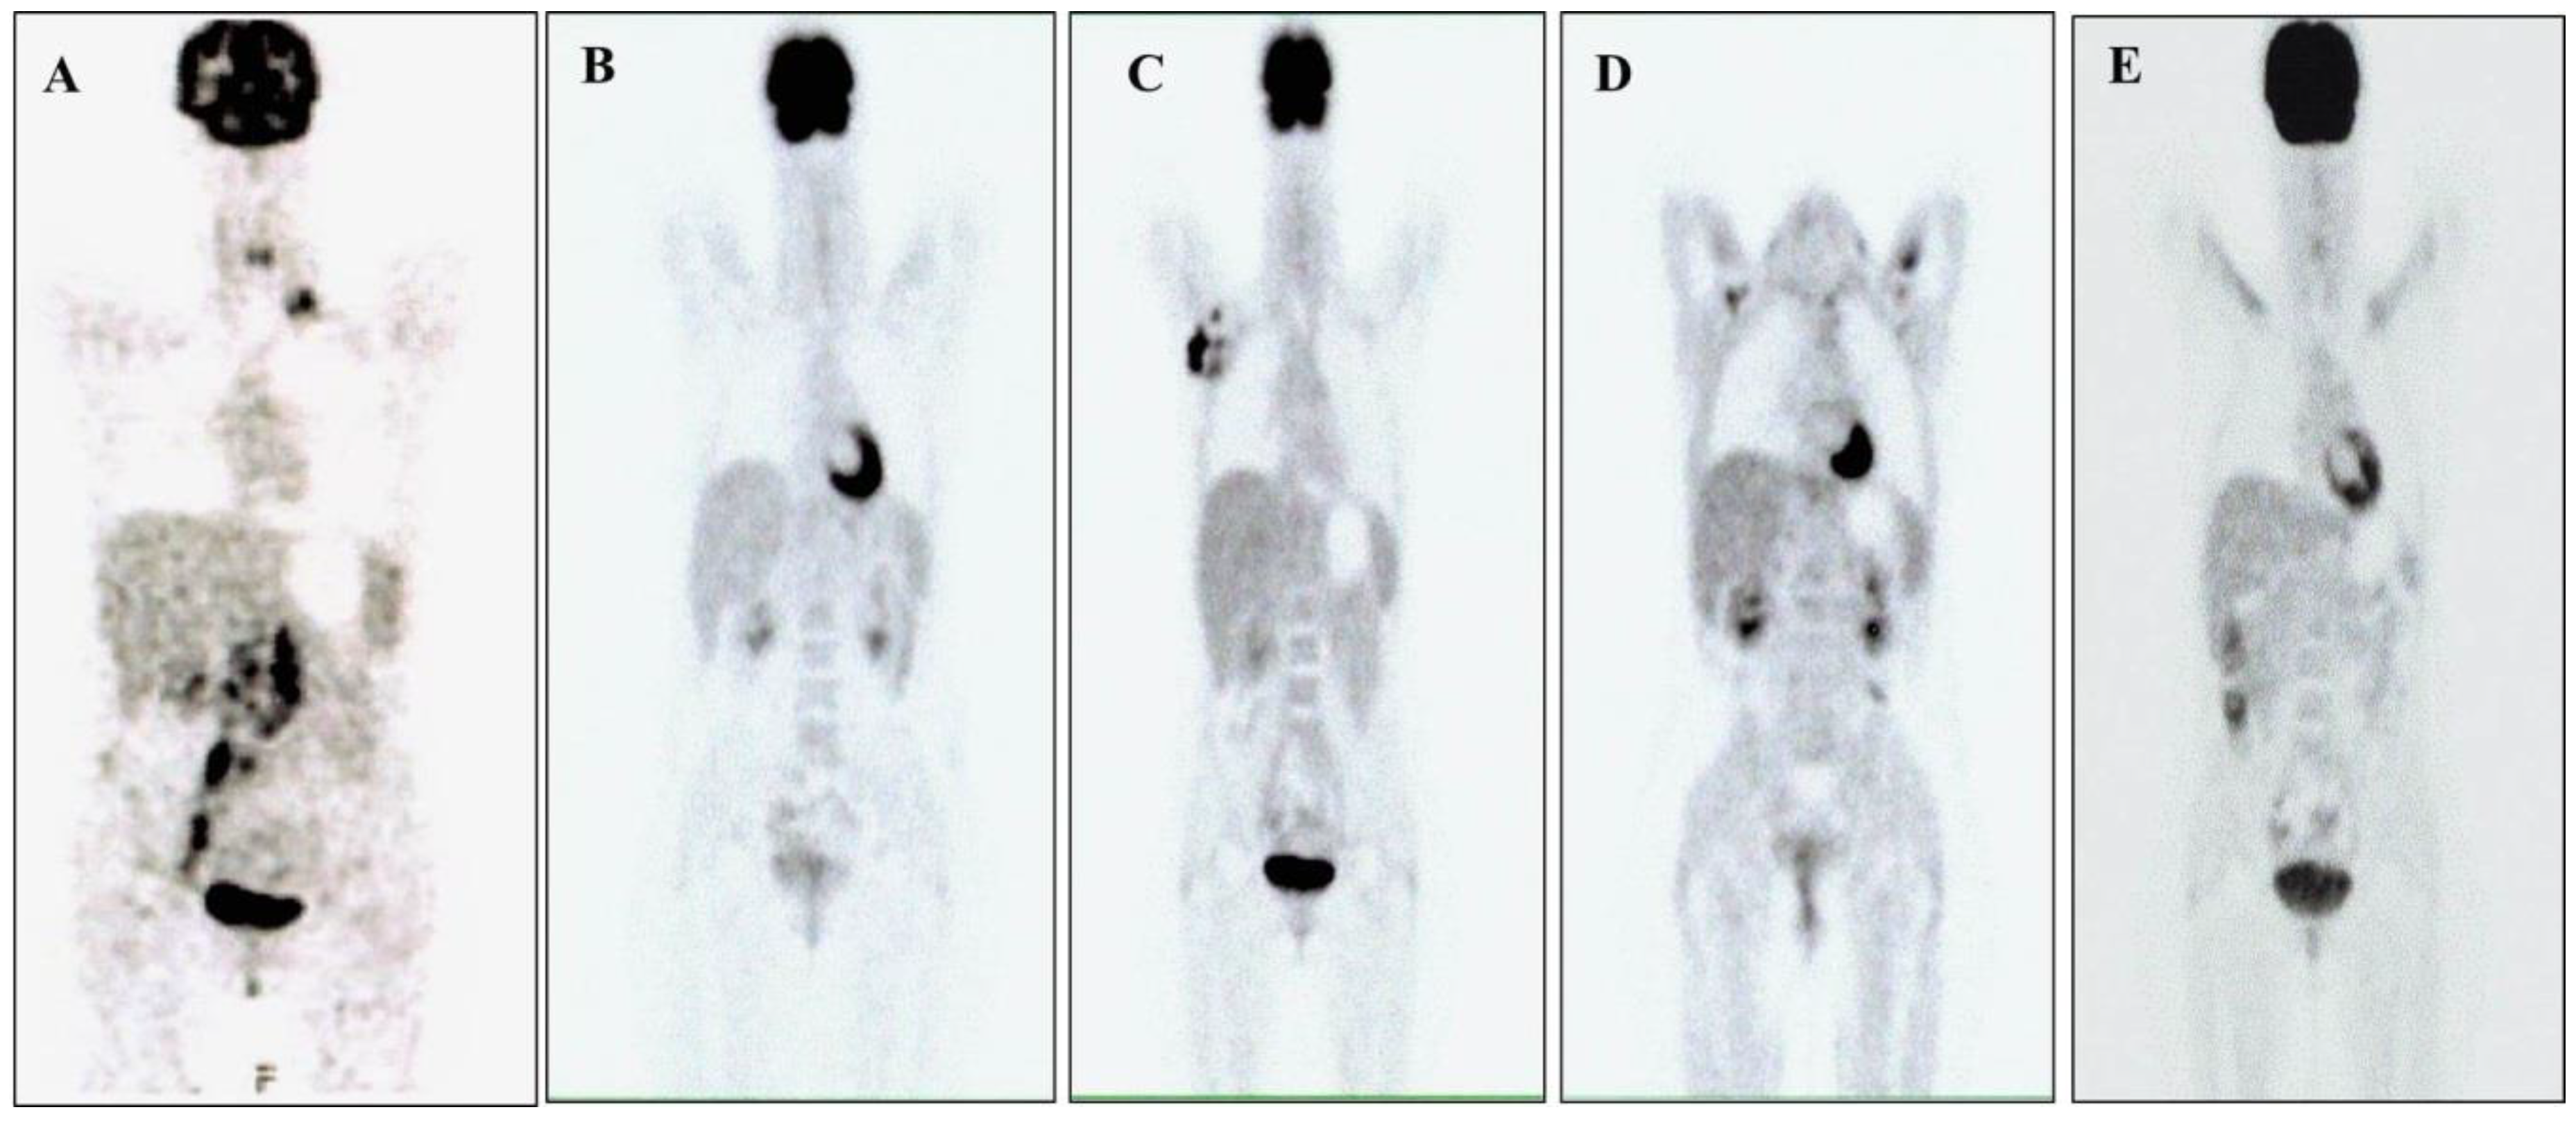

| Period | Therapy |

|---|---|

| From October 2016 to February 2017 | CEOP: 6 cycles |

| From April 2017 to August 2017 | MTX-ARAC-THIOthepa: 4 cycles plus 6 rachicentesis with infusion of MTX, ARAC and steroids |

| From October 2017 to November 2017 | ASCT after HDT with Thio-Bu |

| From July 2019 to June 2020 | Brentuximab: 16 cycles |

| From July 2020 to present | Crizotinib: 250 mg, twice daily |